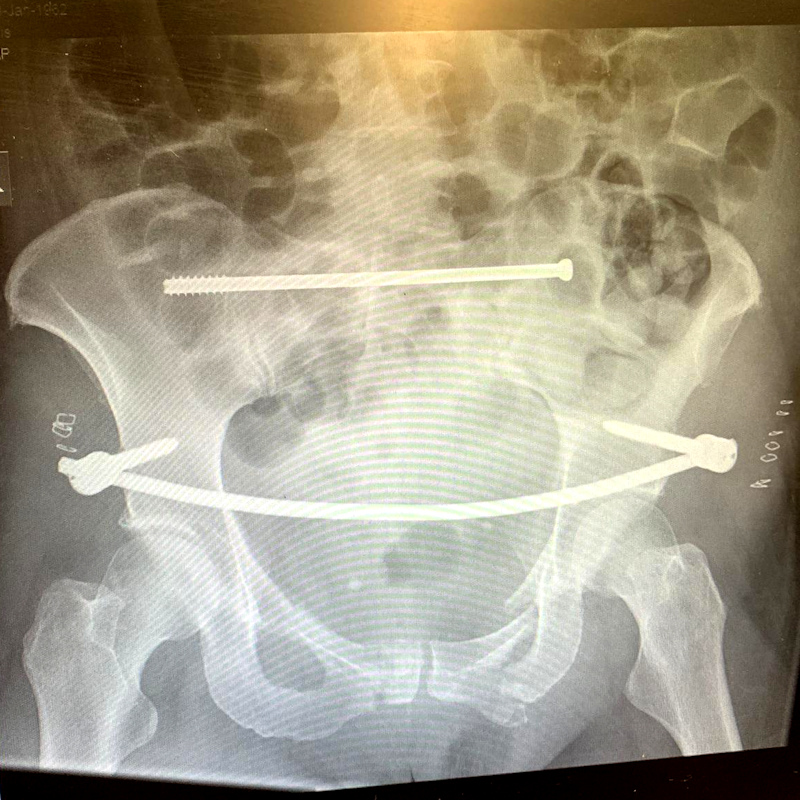

RR’s story: fractured ribs and shattered pelvis.

By the time we saw the calf… it was too late.

The Attack

On the 22nd August, 2019, I was walking with my husband on a popular public footpath near Belper, Derbyshire. There were no warning signs at the entrance to the field, but we saw there were Aberdeen Angus cows in the field. We knew that a lot of people walk through here, so we felt safe. Continue reading “RR’s story: fractured ribs and shattered pelvis.”